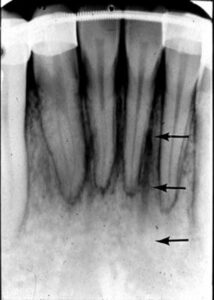

歯科X線写真における正常な解剖学_図5